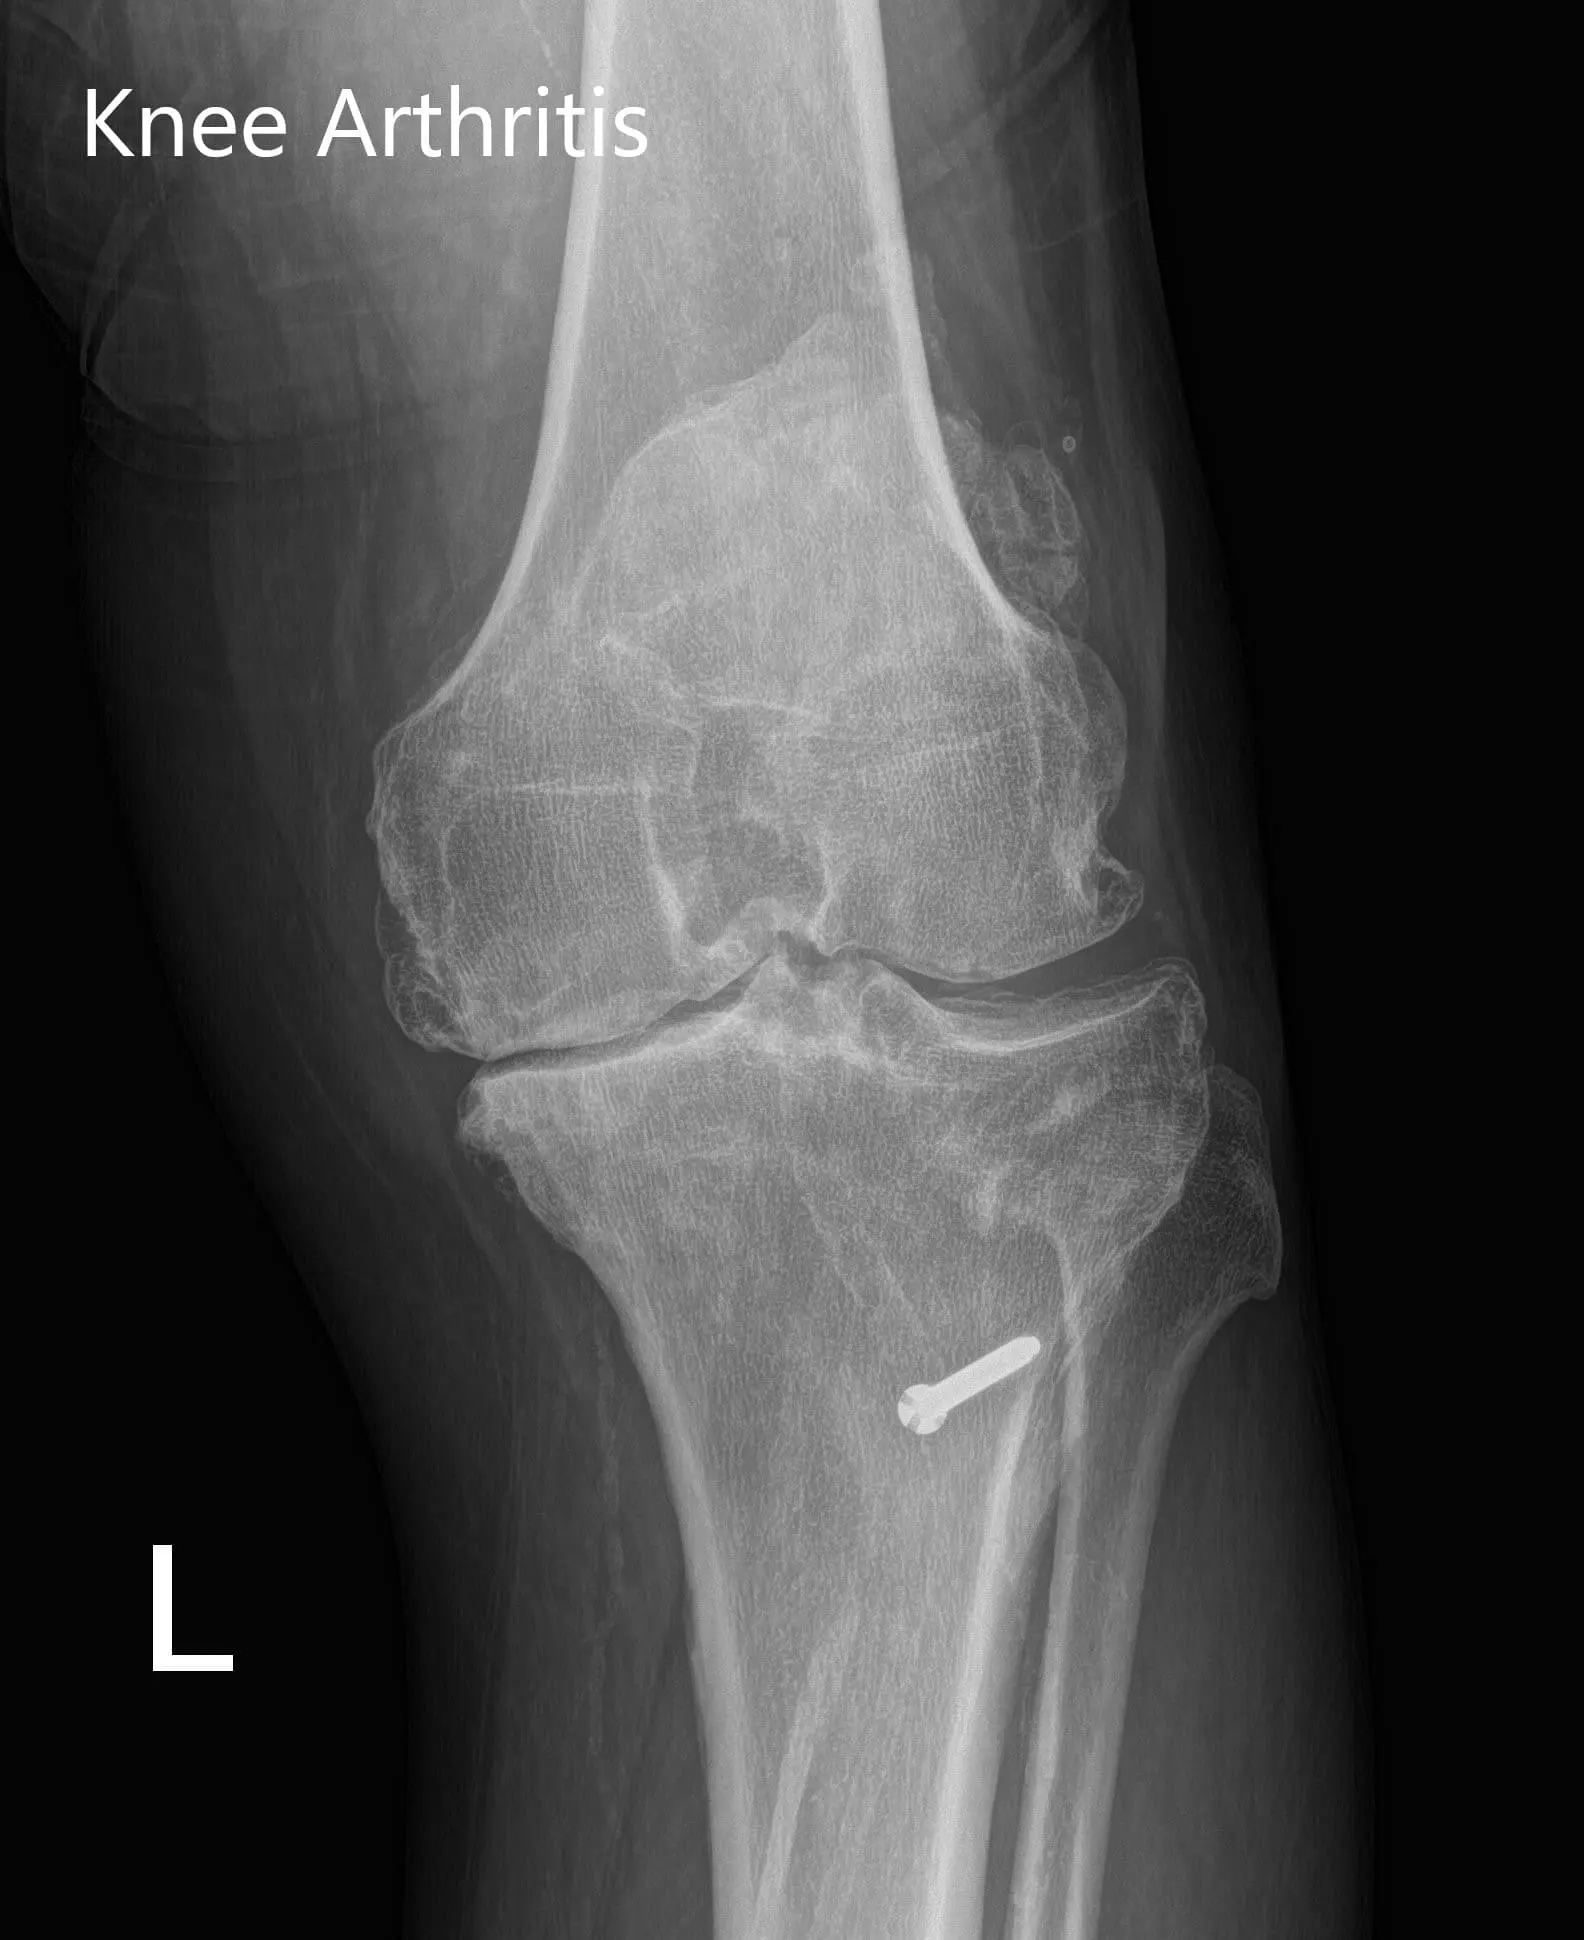

The patient’s physical examination revealed a horizontal scar over the left tibial tubercle. There was mild swelling with genu varus and flexion deformity. The range of motion of the left knee was found to be 10-95 degrees. Medial joint line and medial patellar facet tenderness were elicited. The patient was visibly under distress due to pain. She stated she wanted to explore the options of knee arthroplasty.

Her imaging studies revealed tricompartmental osteoarthritis of the left knee with a retained hardware (bolt) in the left proximal tibia. After assessing her medical conditions and physical examination she was deemed as a candidate for custom knee replacement. She was advised to undergo only the left side in view of the previous history of myocardial infraction and then proceed for right knee.

Preoperative X-ray of the left knee showing AP and lateral views with degenerative osteoarthritic changes and retained hardware in the proximal tibiaPreoperative X-ray of the left knee showing AP and lateral views with degenerative osteoarthritic changes and retained hardware in the proximal tibia - img 2

Preoperative X-ray of the left knee showing AP and lateral views with degenerative osteoarthritic changes and retained hardware in the proximal tibia.